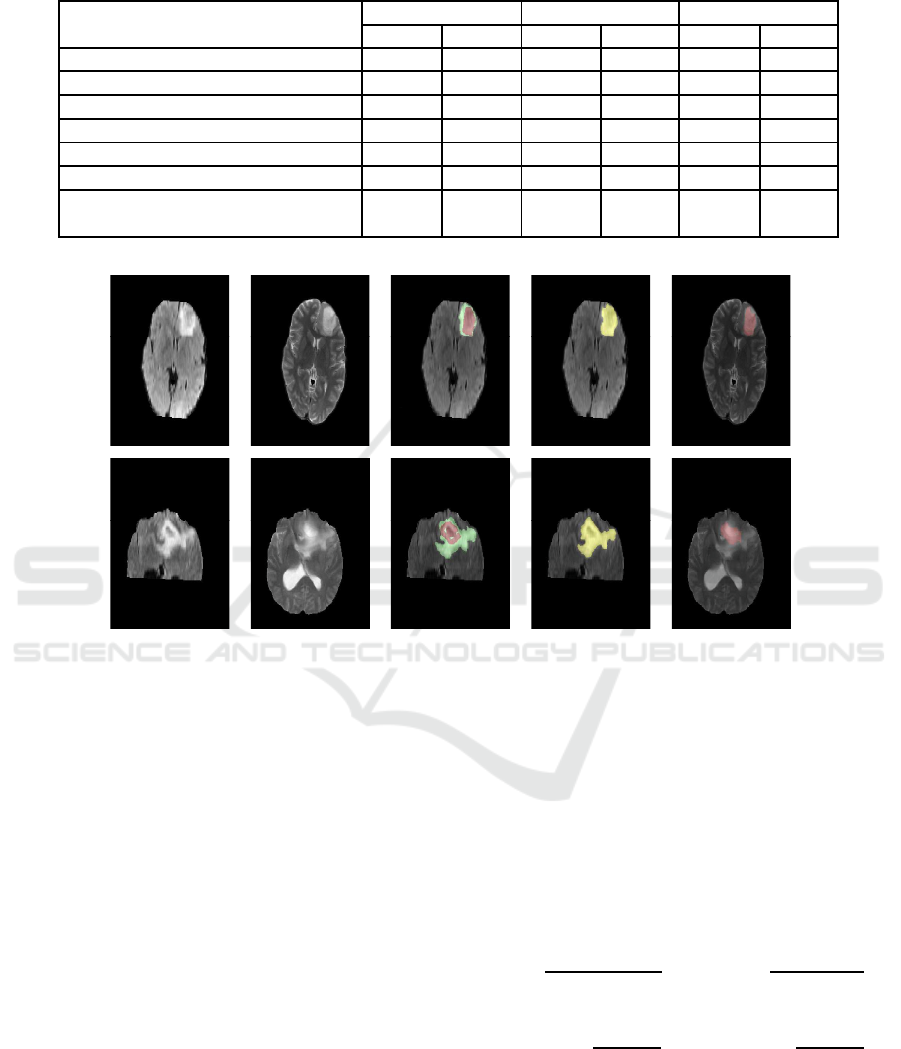

(a) FLAIR slice (b) T2 slice (c) Ground

Truth

(d) Whole

Tumor Segmen-

tation

(e) Necro-

tic Tumor

Segmentation

Figure 3: Segmentation results of L ow Grade Glioma Tumor (Real).

Segmentation resu lts with the proposed alg orithm

are shown in fig. 5, fig. 3, and fig. 4 for High Grade

Real, Low Grade Real and synthetic tumors respecti-

vely. Each row represents (from left to rig ht) FLAIR

slice, T2 slice, Gr ound Truth, Whole tumor segmenta-

tion in FLAI R slice, Necrotic tumor segmentation in